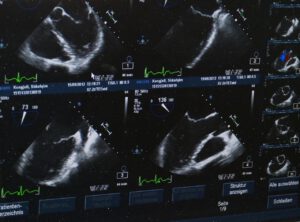

Beim Vorgespräch besprechen wir die Möglichkeiten des Betreuungsplans. Ich bin wie eine Wächterin der Gesundheit von Müttern und Neugeborenen, dafür habe ich jetzt neu, ein leistungsstarkes Systemen zur Verfügung: Ultraschall Vscanair von GE HealthCare. Wir sehen, wie die Schwangerschaft angelegt ist, ob eine Einlings- oder Zwillingsschwangerschaft vorliegt und wie es dem werdenden Menschen geht. Der Ultraschall kann schon ab der 6. Schwangerschaftswoche über den Bauch gemacht werden.